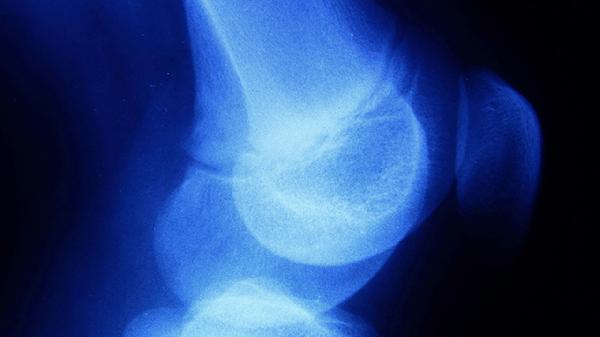

骨膜炎治疗可遵医嘱使用布洛芬缓释胶囊、双氯芬酸钠缓释片、塞来昔布胶囊、硫酸氨基葡萄糖胶囊、活血止痛胶囊等药物。骨膜炎可能与外伤、感染、慢性劳损等因素有关,通常表现为局部红肿、压痛、活动受限等症状。建议及时就医,在医生指导下规范用药。